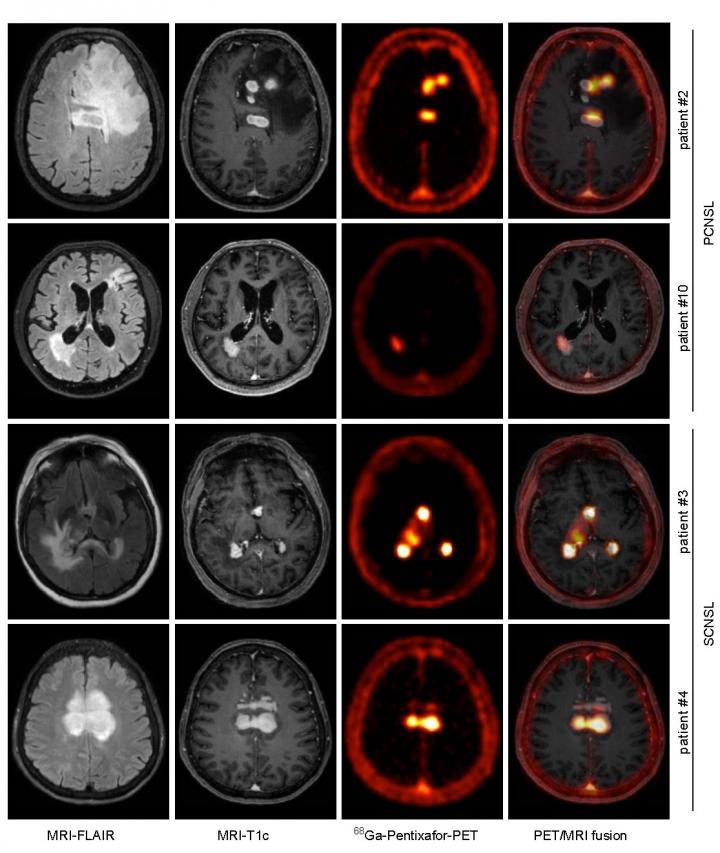

image: CXCR4-directed PET correlates with MRI-determined lymphoma lesions. Depicted are representative MR images (T1c- and FLAIR- sequences), and the corresponding CXCR4- directed PET images and fusion images (MRI-FLAIR and PET), of two patients with PCNSL and SCNSL, respectively.

Reston, Virginia--Positron emission tomography (PET) imaging with 68Ga-pentixafor is an effective diagnostic tool for central nervous system (CNS) B-cell lymphoma, according to a proof-of-concept study published in the December issue of The Journal of Nuclear Medicine. Targeting the CXCR4 biomarker involved in the growth, survival and dissemination of aggressive B-cell lymphoma, 68Ga-pentixafor PET imaging shows excellent contrast characteristics between lymphoma lesions and surrounding healthy brain tissue and may be suitable for risk stratification and response assessment.

CXCR4-directed PET imaging with 68Ga-pentixafor was found to be positive in all active CNS lymphoma lesions, with a high tumor-to-background ratio that offered exceptional contrast. CXCR4 expression in vivo was validated by positive immunohistochemistry for CXCR4; in nine out of 11 patients for whom lymphoma biopsies were available, CXCR4 was highly expressed in the lymphoma lesions. Additionally, CXCR4-directed PET uptake values were found to have a significant prognostic value, indicating that lymphoma lesions with lower CXCR4 tracer uptake values were associated with a better response to standard treatment.